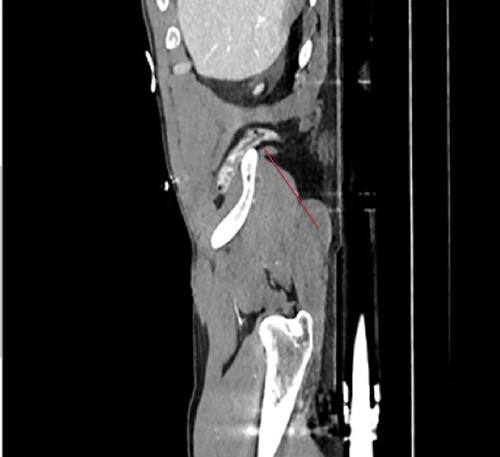

Traumatic lumbar hernias are quite uncommon, as such most surgeons are unfamiliar with them. This was a 41-year-old male Caucasian who was involved in a head on vehicular collision of estimated velocity of 140 mph. Computed tomography (CT) trauma scan confirmed a lumbar hernia through the inferior triangle of petit containing the ascending colon (Figs 1–3). Multiple bony fractures were also noted on the imaging. In discussion regarding the management of the hernia, it was felt that urgent repair was needed to avoid bowel ischaemia or perforation, rather than delayed repair. To repair the defect a laparoscopic approach was initially trialled, (transabdominal repair). Peritoneum was incised around the hernial defect to access the extra-peritoneal space. The hernial sac was dissected; bowels showed no macroscopic signs of ischaemia or injury in the sac. However there was major avulsion of muscles from the iliac crest (>15-cm defect; Fig 1), which was closed posteriorly. Anteriorly it was difficult to close the defect as it was difficult to suture the muscles on to the periosteum of the iliac crest. A decision was made to convert to open surgery as to better access the muscles for suturing. Ventralight mesh was placed extra-peritoneally for further enforcement. The right inferior epigastric vessels were also notably torn, which were tied. Torn right rectus muscles were also approximated and sutured. Peritoneum was closed. This repair was performed extra-peritoneally.

Sagittal view demonstrates the inferior lumbar hernia (red arrow).